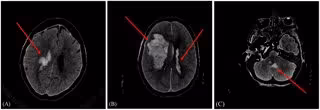

Muestra de imágenes del conjunto de datos tras el preprocesamiento.

Muestra de imágenes del conjunto de datos tras el preprocesamiento. - UNIVERSIDAD DE CANTABRIA